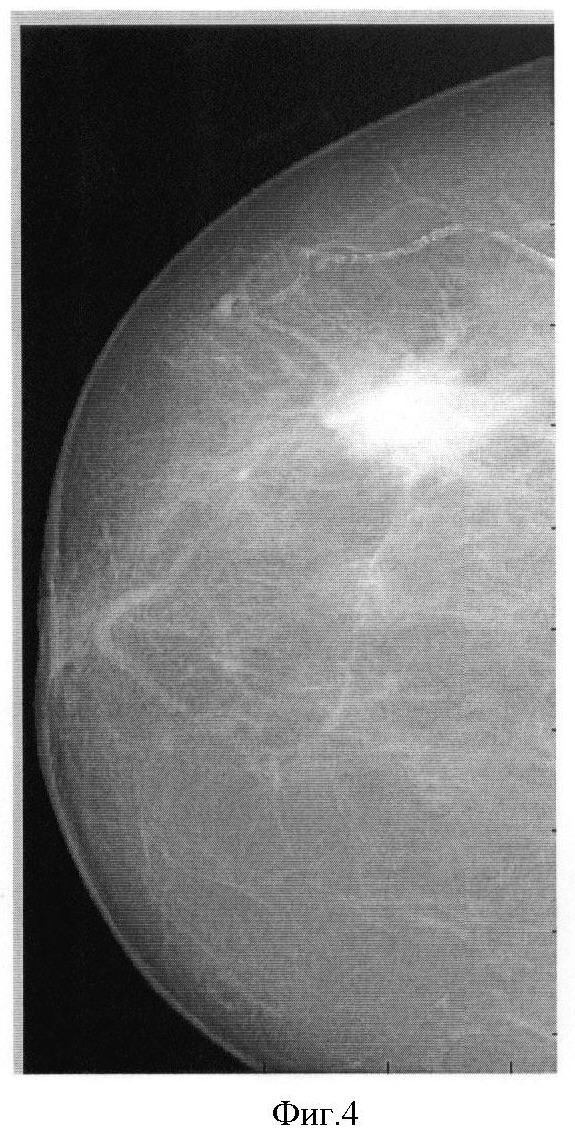

На фиг.1 представлена традиционная молочная железа, на которой прямоугольниками выделены области здоровой ткани (1) и с онкологической тканью (2); на фиг.2 – маммограмма, полученная при использовании способа прототипа; на фиг.3 – зависимость отношения и разности массовых коэффициентов полного поглощения от эффективного атомного номера; на фиг.4 – традиционная маммограмма; на фиг.5 – визуализация распределения эффективного атомного номера; на фиг.6 – традиционная маммограмма (ТМ), эффективный атомный номер (Z), плотность ( ) и их произведение ( Z) онкологической опухоли; на фиг.7 – микрокальцинаты при смещении исходных снимков; на фиг.8 – визуализации распределения идентифицируемого эффективного атомного номера при уменьшении разности энергий излучения; на фиг.9 – визуализации распределения эффективного атомного номера онкологической опухоли при нелинейных преобразованиях исходного распределения числа зарегистрированных фотонов на разной энергии; на фиг.10 – визуализации распределения микрокальцинатов при нелинейных преобразованиях исходного распределения числа зарегистрированных фотонов на разной энергии.

фиг.4 представляет традиционную маммограмму;

фиг.5 представляет идентифицируемое распределение эффективного атомного номера.

Как видно, распределение атомного номера существенно резче и контрастнее традиционной маммограммы.